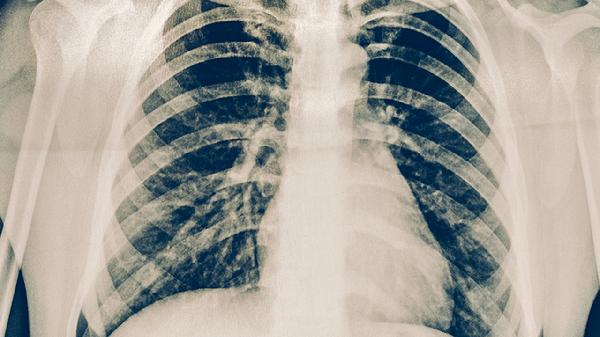

本品含有多味清热解毒药材,可用于肺炎等炎症性疾病的辅助治疗。肺炎常见发热、咳黄痰等症状,使用时需配合抗生素如阿莫西林胶囊、盐酸左氧氟沙星片等药物协同治疗。

药物成分可能通过调控TGF-β等细胞因子抑制肺部纤维组织增生,对肺纤维化有一定改善作用。肺纤维化患者多出现进行性呼吸困难,需联合吡非尼酮胶囊等抗纤维化药物使用。

对支气管扩张、慢性支气管炎等疾病引发的咳嗽、痰多症状有缓解效果。慢性呼吸道疾病易反复发作,用药期间应避免烟雾刺激并预防感冒。